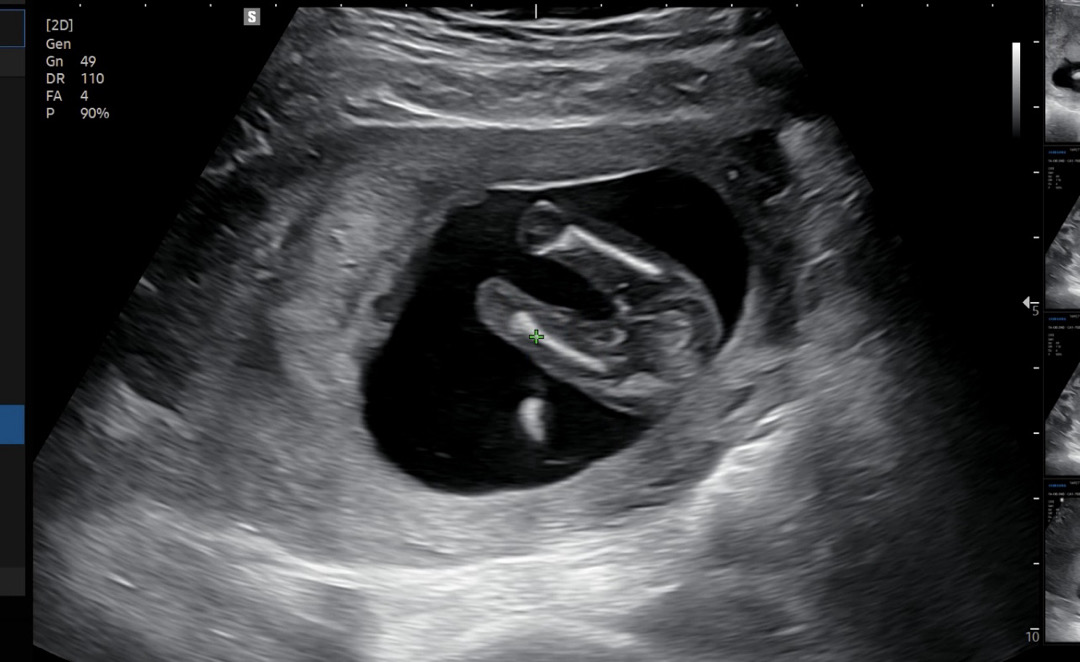

15주 명확하게 성별 보여줬어요😆

원래 2차 기형아 검사까지 2주가량 남았는데 15주면 성별 볼 수 있다길래 서브병원 가니 아가가 잘 움직여서 보여주더라구요! 선생님이 반전없는 여아일거라고ㅎㅎ 첫째는 딸이었음 좋겠다 바라던 바라서 괜시리 기특해요!